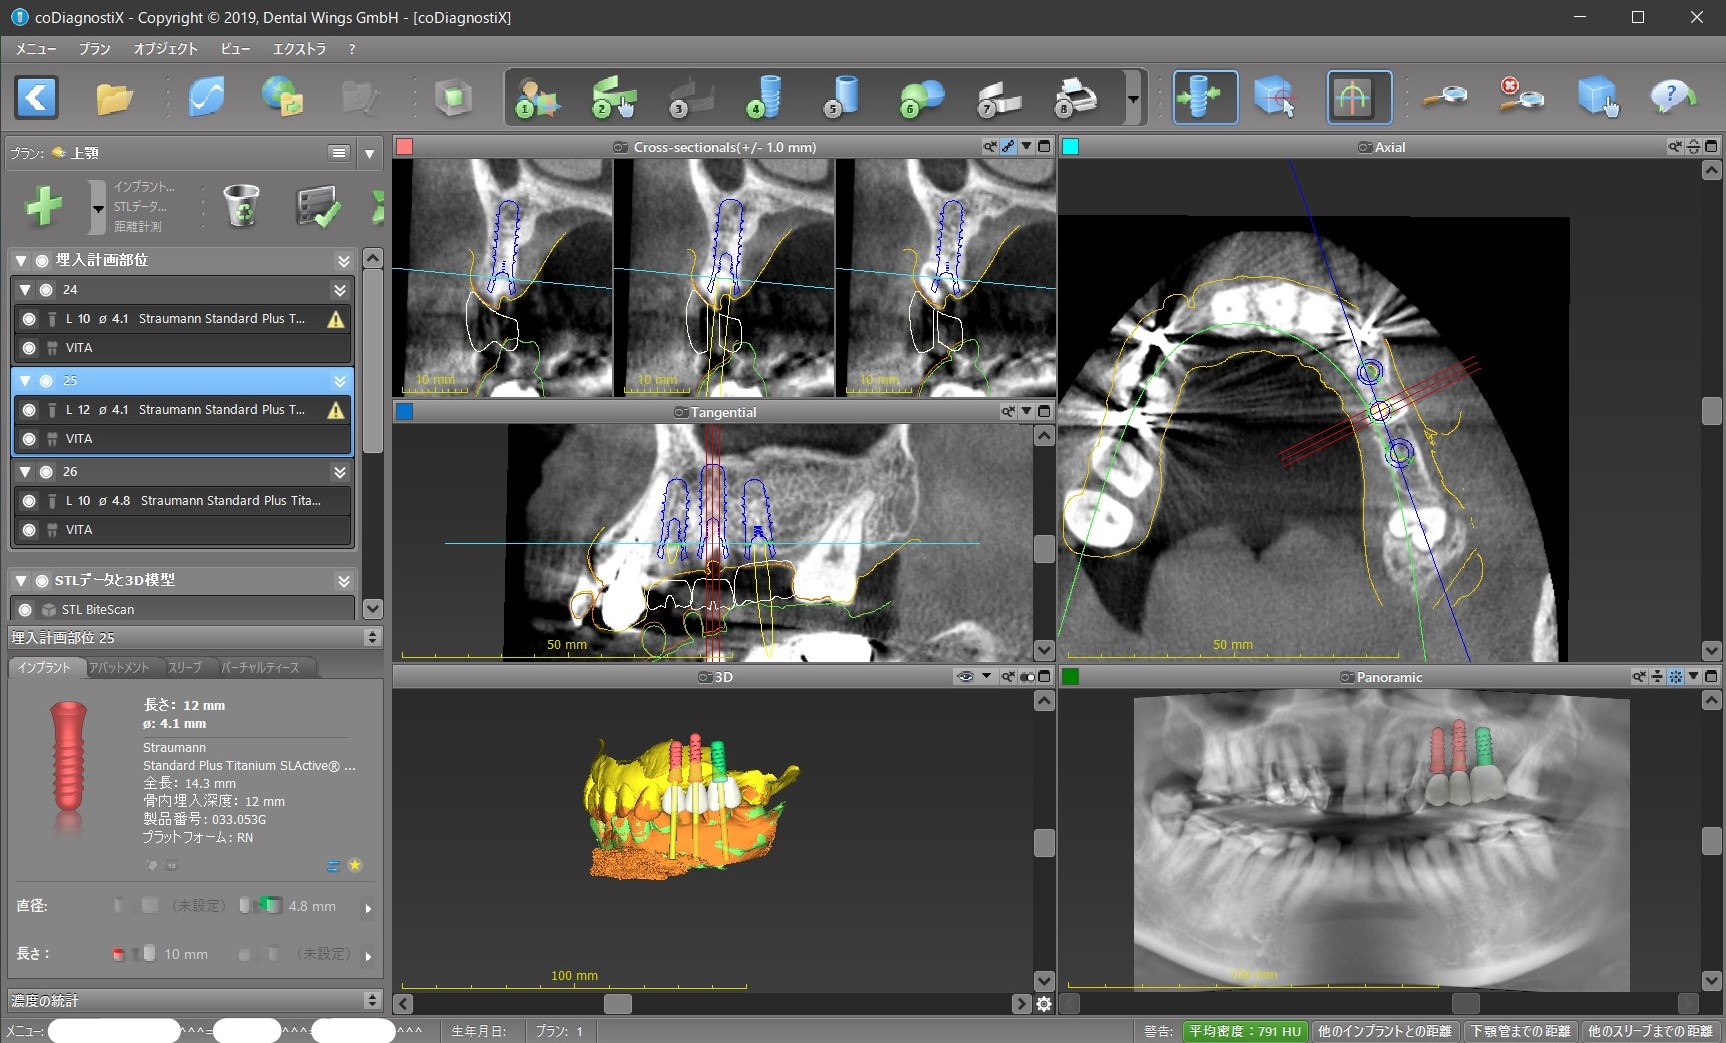

インプラントの位置のシュミレーション

このように、まず先に上部構造の位置をシュミレーションするのです。

先に骨があるところにインプラントを入れて、それから上部構造を作っては、上部構造が上下のかみ合わせが悪いところに来てしまっても手遅れだからです。

今回で言えば、インプラントを前から順に#24、#25、#26と呼ぶと

① #24がその前の天然歯に当たって、そもそもこの位置に入れられない。

② 前述のように#24上部構造が下の歯と咬まない。ちゃんと咬むようにするためには矯正治療が必要になる。

③ #24のインプラントと上部構造との間に角度を付けるか、もしくはGBR(骨を増やす、作る処置)が必要になる。

④ #25インプラント部位に歯の根が残っているので、これをインプラント手術の時に取り除くのと同時にそこに骨を増やす処置が必要になる。

といったところです。